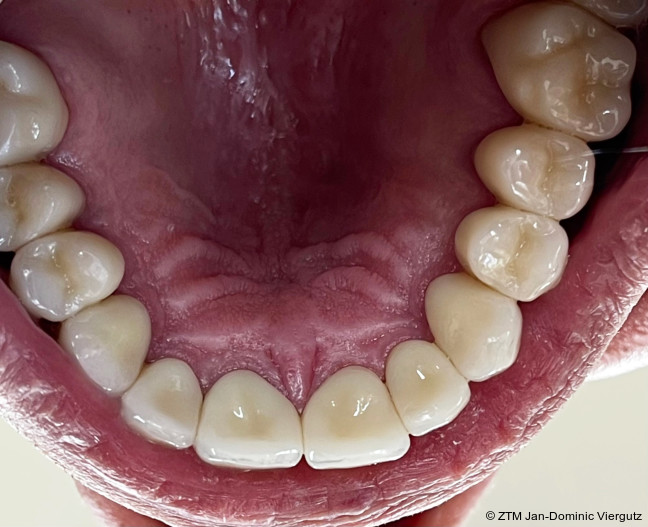

Am folgenden Tag erfolgte eine erneute Konsultation, bei der gemeinsam mit dem Patienten Form und Farbe des Provisoriums evaluiert wurden. Die Zahnfarbe wurde auf VITA A2 angepasst, mit den übrigen Parametern zeigte sich der Patient zufrieden. Diese individuelle Abstimmung garantierte, dass alle relevanten Informationen für die definitive Versorgung vorlagen.Im nächsten Schritt wurden sämtliche digitalen Scans miteinander gematcht (Modellier, Zirkonzahn) und die Modelle via 3D-Druck (Cadspeed) erstellt. Die CAD-Konstruktion der insgesamt 28 Kronen erfolgte mit Prettau 3 Dispersive Multilayer-Zirkon (Zirkonzahn). Für die Frontzähne wurde eine keramische Verblendung (Initial Zr-FS, GC) gewählt, während die Seitenzähne monolithisch mit Prettau 3 Dispersive (Zirkonzahn) gestaltet wurden. Die Bisslage der definitiven Versorgung wurde statisch an die mit der Michigan-Schiene ermittelte Position angepasst. Für die funktionelle Gestaltung der Restauration wurden Gruppenführung und „freedom in centric“ gewählt, um eine physiologische Belastung der Kiefergelenke sicherzustellen.

Der Einsetzprozess der Kronen wurde erneut unter Narkose durchgeführt, um dem Patienten maximalen Komfort und Sicherheit zu bieten. Zunächst erfolgte die adhäsive Befestigung (Multilink Automix, Ivoclar) der Kronen auf den natürlichen Zähnen, wodurch eine stabile und dauerhafte Verbindung geschaffen wurde. Anschließend wurden die Implantatkronen (Prettau 3 Dispersive, Zirkonzahn) mit dem empfohlenen Drehmoment verschraubt.